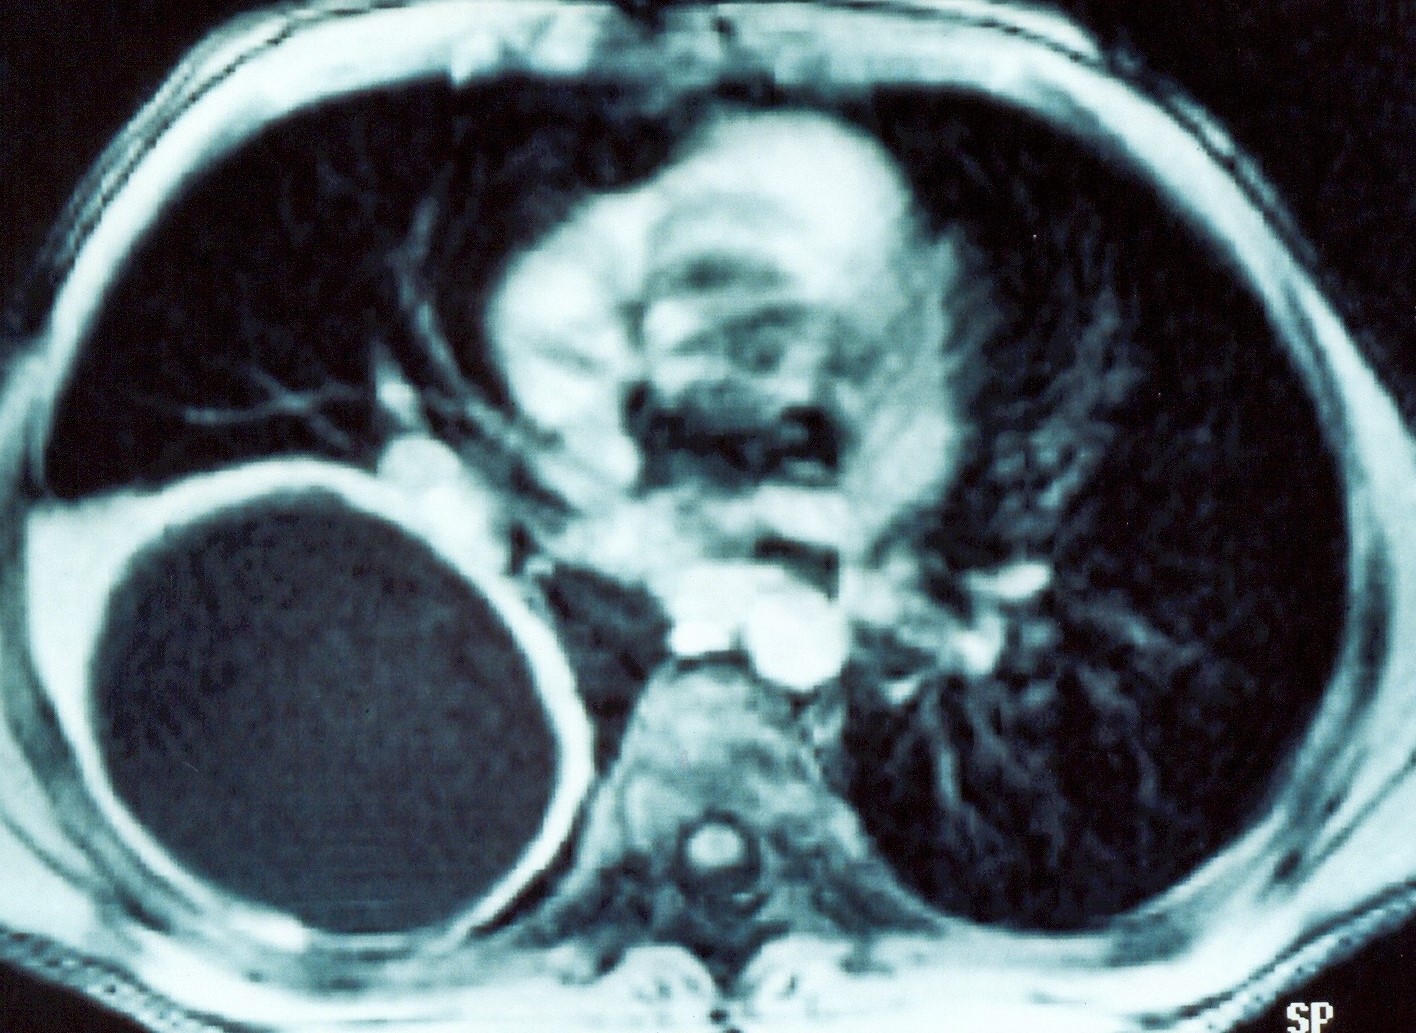

Abdominal computed tomography. Cystic lesion of the right lung. Courtesy Dr. V. Penopoulos.